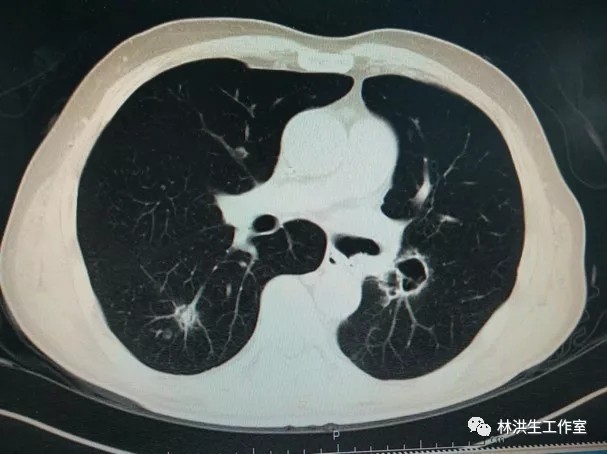

【诊断】左肺下叶腺癌术后双肺转移

【现病史】患者2014年7月就诊于中国医学科学院肿瘤医院诊断左肺下叶腺癌行手术切除pT3N2,术后辅助化疗后不到1年2015年5月复查发现双肺转移,基因检测阴性,中西医结合至今,病灶进展缓慢,体力状况PS 100分。

2017-06中药治疗前:双肺多发转移瘤继续较前增多、增大约1.9*2.3cm

2017-10-21中药治疗后:双肺多发转移瘤大者增大至约2.6*2.3cm